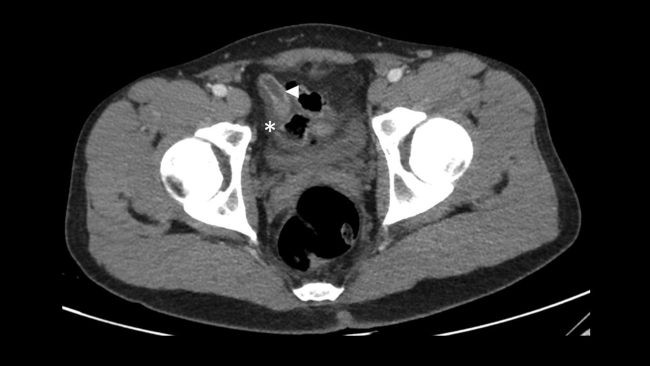

Presentamos el caso de un varón de 30 años que acudió al Servicio de Urgencias de nuestro hospital derivado por su médico de atención primaria, por la presencia de bultomas tumefactos y dolorosos a la palpación, localizados en el cuero cabelludo de un mes de evolución, predominando en zona parietal, temporal y occipital. Asociaba cefalea de características inespecíficas y astenia. Desde hacía dos semanas presentaba nódulos cervicales que impresionaban adenopatías preauriculares, retroauriculares y submandibulares. No presentaba fiebre ni sudoración nocturna. Refería pérdida de 1 a 2 kg en el último mes. Había sido tratado con minociclina 100 mg durante un mes sin mejoría. Durante su estancia, se realizó interconsulta con el Servicio de Dermatología, que completó el estudio con serologías de sífilis, virus de la inmunodeficiencia humana (VIH), hepatitis y citomegalovirus; biopsia de las lesiones de cuero cabelludo, cuyo resultado reveló linfoma / leucemia linfoblástica T; y se practicó punción aspirativa con aguja fina (PAAF) de adenopatía cervical, que confirmó el cuadro linfoide monomorfo. También se solicitó TC toracoabdominopélvica con contraste intravenoso (CIV) que puso de manifiesto: una masa mediastínica anterior que englobaba vasos con leve compresión y desplazamiento sugestiva de conglomerado adenopático y múltiples lesiones focales renales, bilaterales, así como engrosamiento apendicular sugestivos de infiltración linfomatosa (►Figs.1,2a,2b,3a,3b).

En cuanto al linfoma apendicular, es poco frecuente y difícil de sospechar en ausencia de otros hallazgos linfomatosos.4 La etiología más frecuente es por extensión de un linfoma cecal hacia la base apendicular.5 Las manifestaciones clínicas típicas son similares a las de la apendicitis aguda y la TC también es de elección.5 El apéndice puede agrandarse masivamente, pero generalmente mantiene su apariencia.5 El engrosamiento mural difuso tiene atenuación de tejido blando en la TC.4 La tomografía por emisión de positrones (PET) con fluordesoxiglucosa puede demostrar una captación anormal e intensa del radiotrazador en la región del apéndice.6